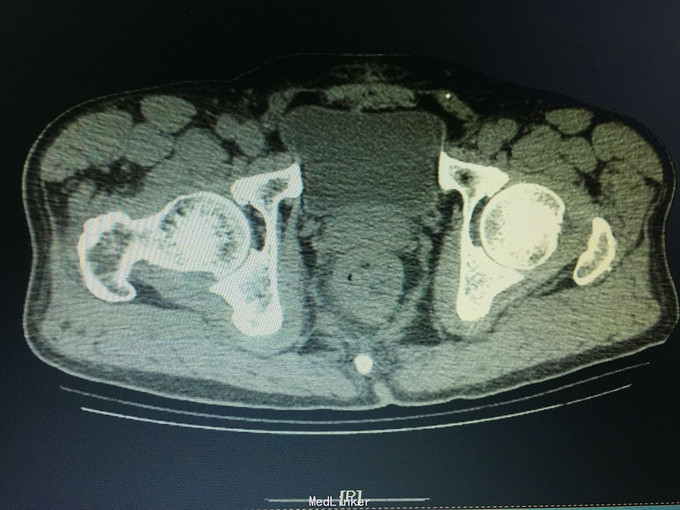

一般状态好,无贫血貌,肛门外缘不规整,肛门指诊:距肛缘4cm可及溃疡性肿物,近环形,固定,指套染陈旧血。 辅助检查:盆腔CT:直肠管壁不规则肥厚,官腔偏心性狭窄,周围见条索影及结节影。

诊断:直肠癌, 预约结肠镜检查:距肛缘4cm见环肠肿物,凸凹不平,表面覆污秽苔,质硬,界不清。 病理结果为直肠腺癌。 病人回当地医院接受治疗。